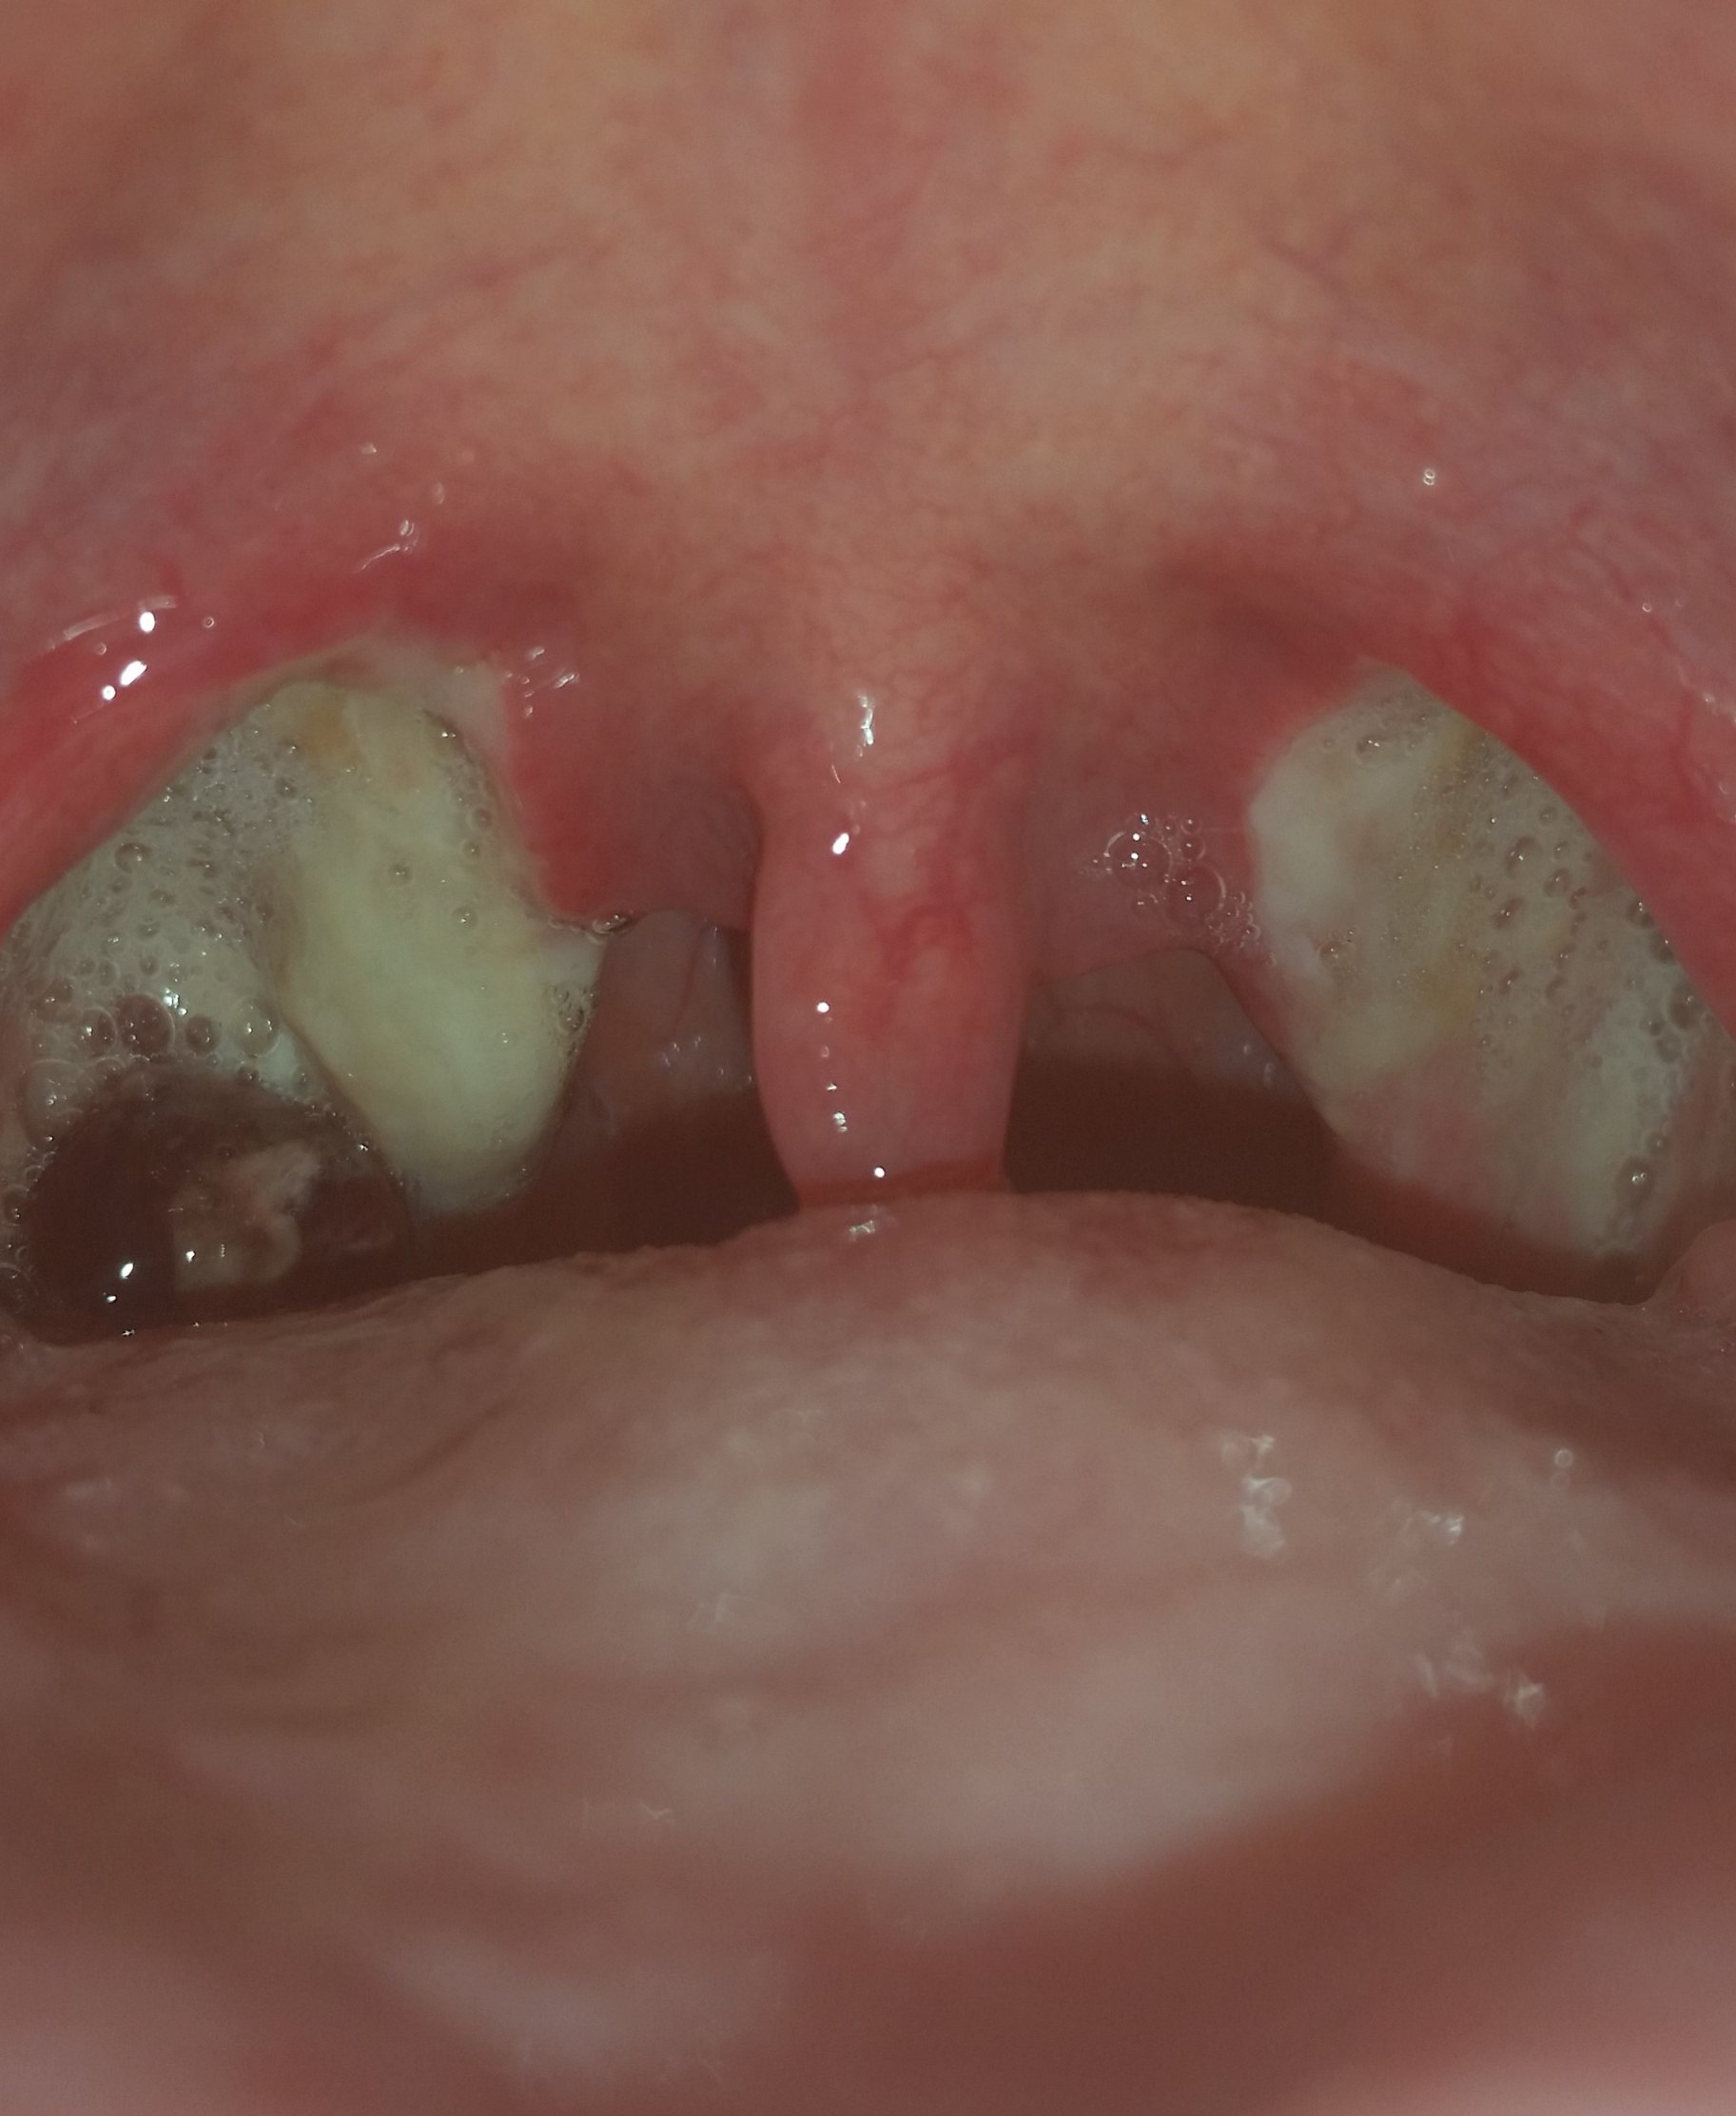

Mandel OP – Bilder Dokumentation Heilungsprozess

- Mandeloperation Tag 1

Nach der Operation bildeten sich direkt die weiß, grünlichen Beläge (Fibrinbeläge).

Bis sich die Beläge lösten hatte ich einen leicht „fauligen Mundgeruch“.